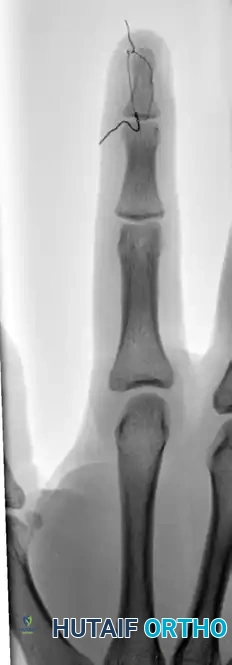

FIGURE 67-64 A and B: Displaced and angulated distal phalangeal fracture associated with a severe nail bed laceration in a 22-year-old patient, demonstrating the classic presentation of a complex open distal phalanx injury.

FIGURE 67-64 C and D: Postoperative radiographic and clinical appearance after precise bone fixation with a K-wire, which provided the necessary stability to permit subsequent realignment and microsurgical repair of the nail bed.